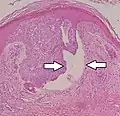

Nodular basal-cell carcinoma

Nodular basal-cell carcinoma (also known as "classic basal-cell carcinoma") accounts for between 50% and 80% of all BCC.[2] It most commonly occurs on the sun-exposed areas of the head and neck.[2] Histopathology shows aggregates of basaloid cells with well-defined borders, showing a peripheral palisading of cells and one or more typical clefts.[17] Such clefts are caused by shrinkage of mucin during tissue fixation and staining.[18] Central necrosis with eosinophilic, granular features may be also present, as well as mucin. The heavy aggregates of mucin determine a cystic structure. Calcification may be also present, especially in long-standing lesions.[17] Mitotic activity is usually not so evident, but a high mitotic rate may be present in more aggressive lesions.[17] Adenoidal BCC can be classified as a variant of NBCC, characterized by basaloid cells with a reticulated configuration extending into the dermis.[17]

- Cleft.